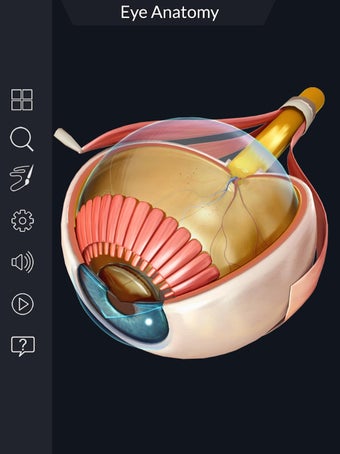

Изучите в деталях человеческий глаз и его анатомию с помощью этого простого в использовании бесплатного приложения для Android. Он позволяет масштабировать и вращать на 360° вокруг высокореалистичной 3D-модели глаза, а также рисовать на экране или прослушивать звуковое произношение каждого термина.

Вы можете выбрать X- просмотр луча, скрытие и отображение отдельных частей глаза, а также рисование или белый цвет на экране и обмен снимками экрана, звуковое произношение для всех анатомических терминов и многое другое.

Каждая часть разделена на отдельный вид, где вы можете можно увидеть название детали и ее расположение на глаз.